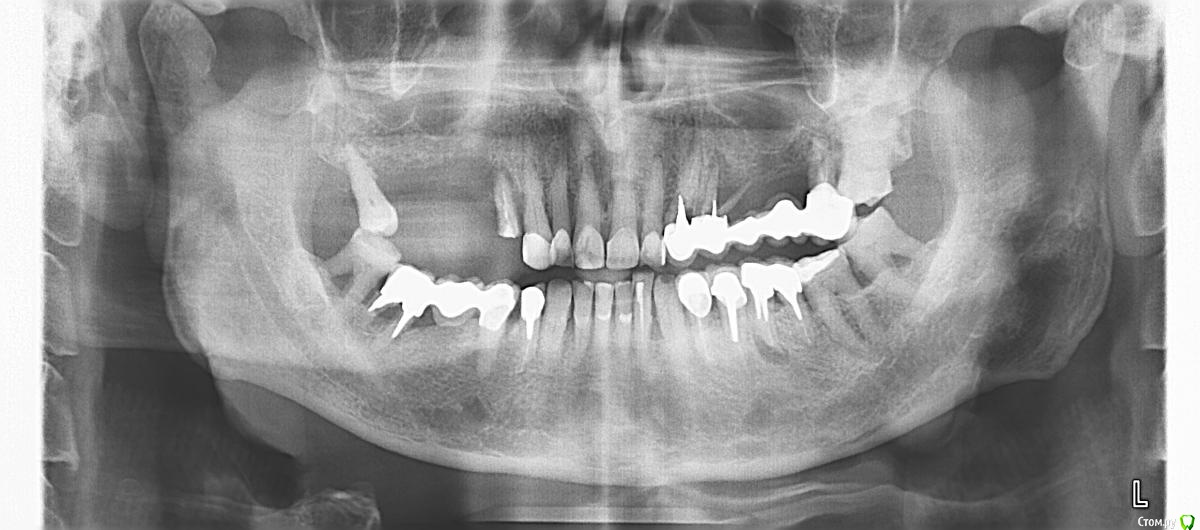

Serg2018 Опубликовано 24 ноября, 2018 Автор Поделиться Опубликовано 24 ноября, 2018 (изменено) Виноват. Вот файл с диска, я его уменьшил до 200 кв. Левый мост тоже под удаление и имплантацию, он держится на одном зубе 7-ке, я им жую. Изменено 24 ноября, 2018 пользователем Serg2018 Ссылка на комментарий

Bier Опубликовано 24 ноября, 2018 Поделиться Опубликовано 24 ноября, 2018 у вас не очень простая ситуация с точки зрения эстетики. Если хочется, чтобы зубы были нормального размера, придется костную пластику делать, потом уже имплантация. Шаблон желателен опять же для эстетики. 1 Ссылка на комментарий

Serg2018 Опубликовано 26 ноября, 2018 Автор Поделиться Опубликовано 26 ноября, 2018 Имеется ввиду справа, чтоб коронки не пришлось делать длинными или с обеих сторон? Спасибо. Ссылка на комментарий

Bier Опубликовано 26 ноября, 2018 Поделиться Опубликовано 26 ноября, 2018 да, справа. слева получше ситуация Ссылка на комментарий

Nazim_NV86 Опубликовано 29 ноября, 2018 Поделиться Опубликовано 29 ноября, 2018 (изменено) КЛКТ от 04.05.18г 8х8см. Что изменилось на сегодняшний день ? Какое то лечение/удаления было проведено с мая ? Тут не до шаблонов пока. Синусит двусторонний в том числе. Изменено 29 ноября, 2018 пользователем Nazim_NV86 Ссылка на комментарий